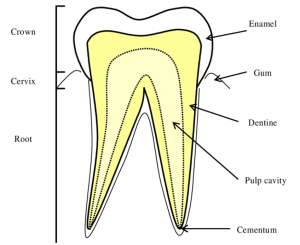

충치 치료의 종류에 대해 알아보기전에 치아의 구성 조직들에 대해 이해하는 것이 필요합니다. 어려울 것 없는데요. 그 구성 조직들이 충치에 감염되는 범위에 따라 충치 종류가 나눠진다고 보시면 되겠습니다. 아래는 치아의 구성 요소입니다.

- 에나멜

- 상아질

- 치수

- 치근

여기서 에나멜은 흔히 말해 겉으로 보이는 가장 바깥쪽의 매우 단단한 하얀색 치아를 말합니다. 그냥 거울을 통해 보았을 때, 육안으로 바로 보이는 것이 에나멜이라고 보시면 되겠습니다. 에나멜이 감염되면 그냥 깍아서 레진 충전을 통해 치료만 하면 됩니다. 가장 경미한 단계이죠.

그 다음 상아질은 에나멜의 내부라고 보시면 되는데요. 미네랄 함량이 적기 때문에 에나멜보다는 부드러운 조직에 속하며 이 때부터 중간 단계라 보시면 됩니다. 상아질에는 관이 있기 때문에 세균이 더욱 빠르게 확산되는데요. 그래서 겉으로 보이는 충치보다 실제 충치는 더욱 큰 범위로 확산되어있는 것이죠.

마지막으로는 치수 입니다. 치아 내부의 연조직으로써 신경과 혈관이 모여있는 곳을 말합니다. 즉 이 때부터는 신경치료의 범위에 해당 하게 됩니다. 이 때 두가지로 나눌 수 있는데요. 신경치료는 다행히 근관치료를 통해 자연치아를 보존할 수 있지만, 감염이 심할 경우 발치와 같은 침습치료가 필요할 수 있습니다.